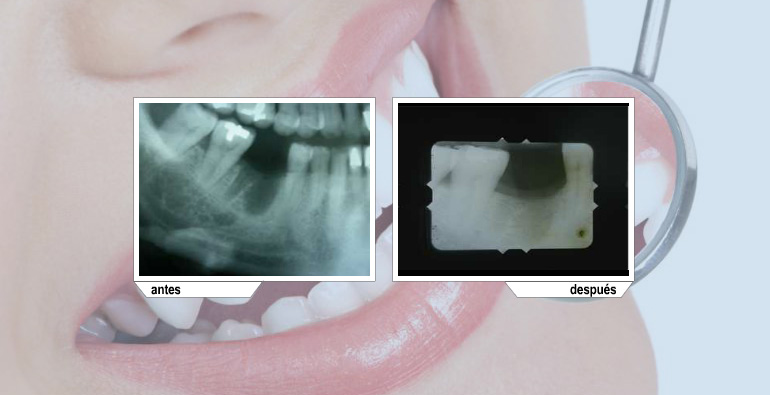

En los casos de pérdida dental la mejor restauración que podemos ofrecer es por medio de implantes dentales. Siempre se deberá contar con la mejor tecnología para minimizar el margen de error.